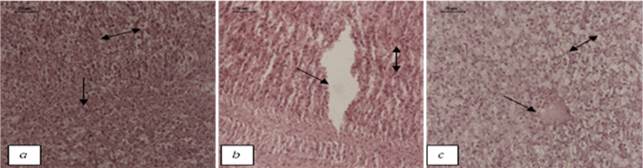

Transverse sections of H. fossilis liver at pH 7±0.5 after 36 hour-H&E-40X (a) Control: Normal hepatocytes (single headed arrow); Sinusoids (double headed arrow) (b) Copper treated: Degradation of cellular hepatocytes (single headed arrow); sinusoids with pyknotic nuclei (double headed arrow) (c) Cadmium treated: Necrosis (single headed arrow); Sinusoids (double headed arrow)

Fig: Transverse sections of H. fossilis liver at pH 7±0.5 after 36 hour-H&E-40X (a) Control: Normal hepatocytes (single headed arrow); Sinusoids (double headed arrow) (b) Copper treated: Degradation of cellular hepatocytes (single headed arrow); sinusoids with pyknotic nuclei (double headed arrow) (c) Cadmium treated: Necrosis (single headed arrow); Sinusoids (double headed arrow)